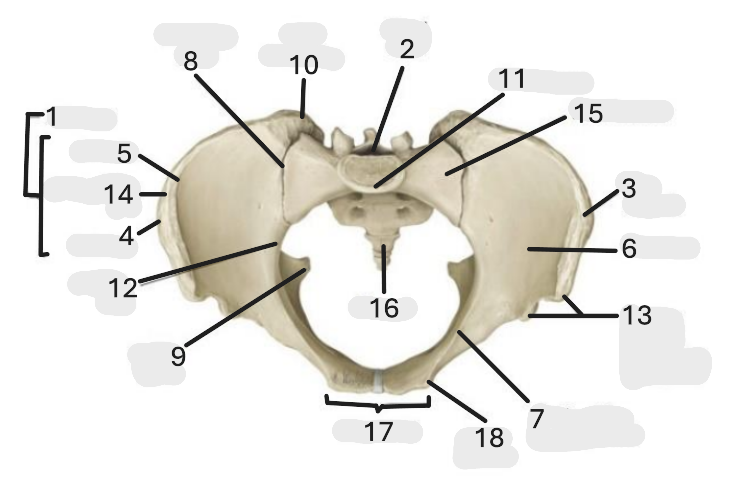

Where is the pelvic inlet

1

Where is the sacro-iliac joint

2

Where is the pubic tubercle

3

Where are the S1 body

4

Where is the ischial spine

5

Where is the ala of sacrum

6

Where is the anterior superior iliac spine

7

Where is the ischiopubic ramus

8

Where is the coccyx

9

Where is the obturator foramen

10

Where is the pubic symphysis

11

Where is the ischial tuberosity

12